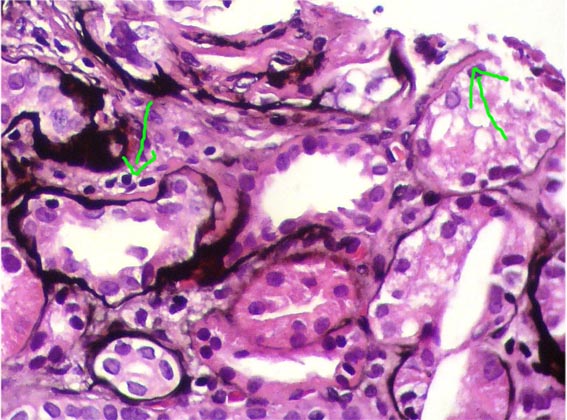

Figura 8.

PAS, X400.

Figura 9.

Plata-metenamina, X400.